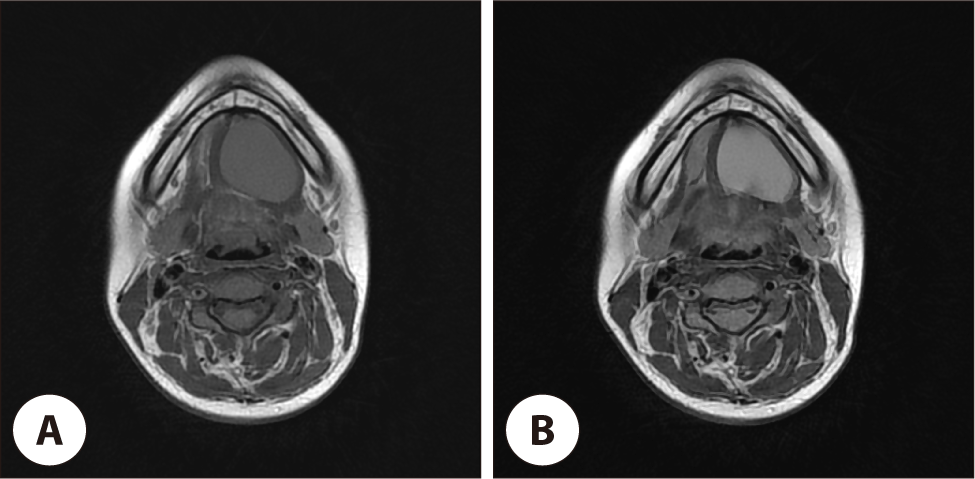

jcohns-37-1-17-g3

Fig. 3. Preoperative MRI scans. Pre-operative MRI scan shows 3.1×3.3×3.7 cm, well defined mass at left submandibular area with intermediate/slight high signals in (A) T1, (B) T2WIs with no significant solid portion.

Download Original Figure

14세 여자 환자로 수년 전부터 턱 밑 종물이 있었으며 별다른 치료 없이 경과관찰 하였으나, 약 6개월 전부터 점차 크기가 증가하는 양상 보여 본원 이비인후과를 내원하였다. 특별히 호소하는 다른 증상은 없었고, 이학적 검사 상 4×3 cm 크기의 부드러운 종물이 만져졌으며 고정되어 있는 양상이었다. 내시경 상 구강저 점막은 정상 소견을 보였으며, 염증 소견 및 기타 유의미한 해부학적 변화는 관찰되지 않았다(Fig. 1A). 전산화단층촬영(computed tomography, CT) 상 3.7×3.3 cm 크기의 주위와 경계가 분명한 종괴가 관찰되었고, 일부 종괴는 하악설골근을 뚫고 아래로 전위되어 있었으며 종괴 내부는 저음영을 보이고 있었다. 조영 증강시에도 내부는 조영 증강이 되지 않는 소견이었다(Fig. 2). 임상적으로 몰입형 하마종이 의심되었으나, 수년간 지속된 턱 밑 종괴의 병력을 고려할 때 설하선 기원의 Warthin 종양 및 기타 양성 종양의 가능성을 배제할 수 없었다. 이에 질환의 감별 및 해부학적 연관성 파악을 위해 경부 자기공명영상 촬영을 시행하였다. 경부 자기공명영상(magnetic resonance imaging, MRI) 소견상 좌측 악하부에서 명확한 경계를 가진 3.1×3.3×3.7 cm 크기의 병변이 관찰되었으며, 이는 T1 및 T2 강조영상 모두에서 중등도 내지 약간의 고신호 강도를 나타내었고 유의미한 고형 성분(solid portion)은 동반하지 않았다(Fig. 3). 이러한 소견은 단백질이나 점액 함량이 높은 낭성 병변(cystic lesion)의 가능성을 시사하였으며, 고형 성분의 부재는 Warthin 종양보다는 몰입형 하마종을 좀더 시사하는 소견이었다. 몰입형 하마종 의증 하에 확진 및 치료를 위해 수술적 절제를 결정하였다. 환자 보호자가 재발률을 최소화할 수 있는 치료법을 희망함에 따라 하마종의 기원으로 추정되는 설하선을 절제하는 동시에 조대술을 시행하는 수술을 계획하였다. 구강 내 접근법을 이용하였으며 혀와 구강저의 연결부인 설소대를 따라 절개를 넣고 박리하여 종괴에 접근하였다. 구강저의 점막을 박리한 후 노출된 종괴는 육안상 일반적인 하마종의 일반적인 성상과는 달리 백색의 피막에 싸여진 부드러운 고형성 종물로 확인되었다(Fig. 4A). 술 중 설신경 및 악하선관을 확인하여 보존하였으며, 주변 조직과의 유착이나 침범 소견이 없어 설하선을 온전하게 보존하며 종괴를 완전 절제하였다. 동결절편검사는 시행하지 않았다. 환자는 수술 후 3일째 특별한 합병증이 보이지 않아 퇴원하였다.